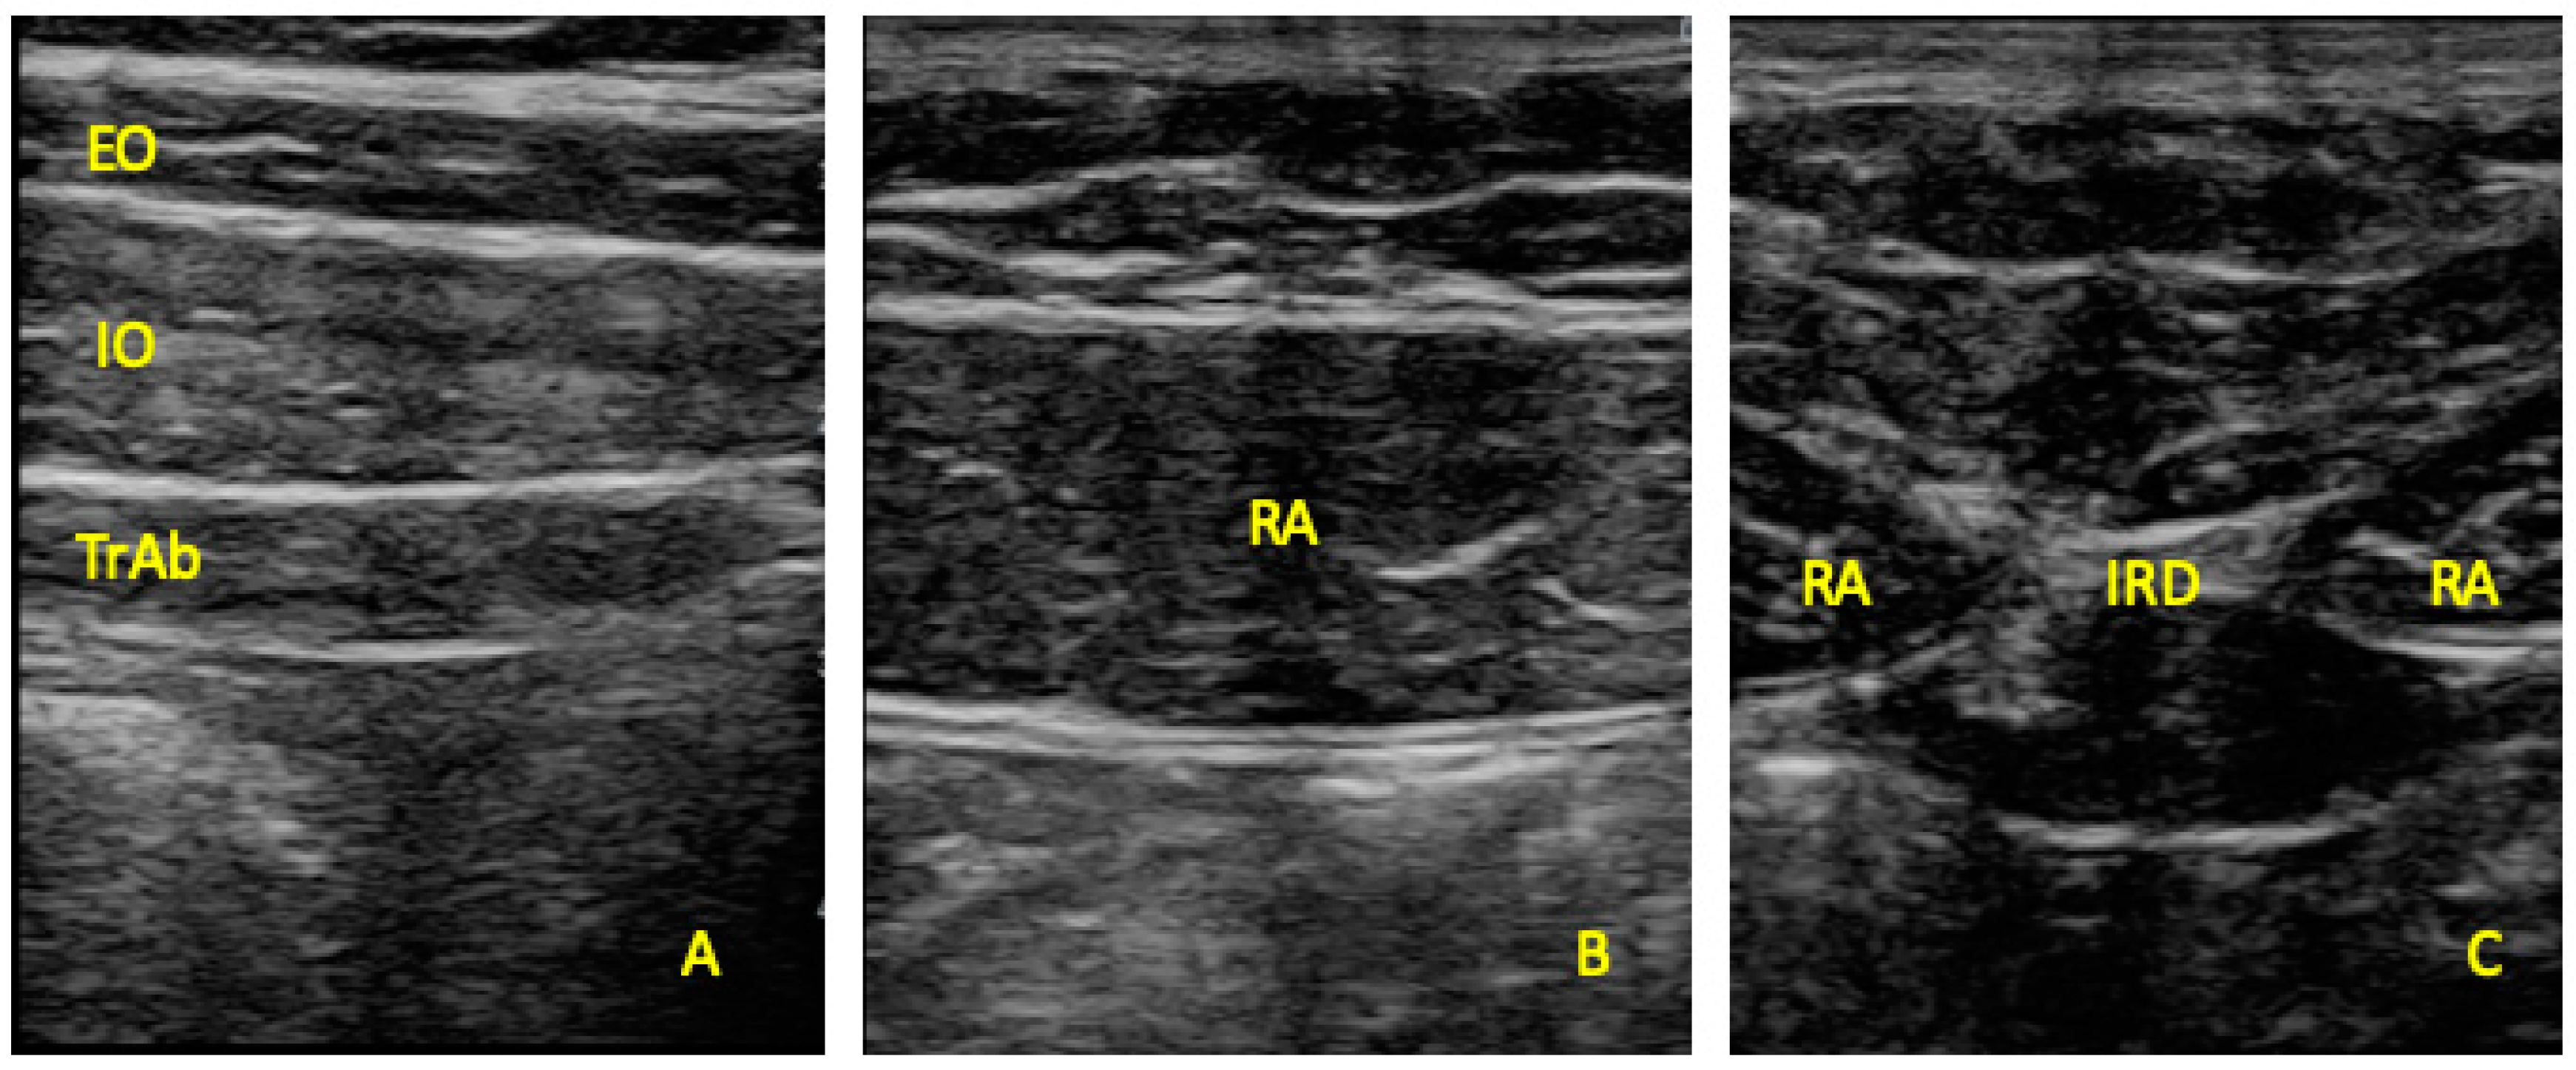

Ultrasonography was developed with a LogiQ ultrasound system (GE, Healthcare, UK), with a 4–13 MHz linear transducer (38-mm footprint) for the anterior abdominal wall muscles and with a 2–5.5 MHz convex transducer (38-mm footprint) for the multifidus evaluations. All the evaluations were developed by the same therapist (P.M.L.), with 3 years of experience in ultrasound imaging of the musculoskeletal field. All the images for the anterior abdominal muscles were taken in supine position. The images of the EO, IO, and TrAb muscles was developed by placing the transductor in the mid-axillary line, between the subcostal line and the iliac crest [9] (Figure 1A). For the RA muscle examination, the transducer was placed aligned with the umbilicus, and just under the umbilicus for the IRD evaluation (Figure 1B). Muscle thickness was considered as the distance between the edges of each muscle and IRD was described as the distance between the both RA muscles [9]. For the multifidus muscles examinations patients were placed lying in prone position at rest and during a maximal isometric contraction with the ipsilateral extended lower limb for 5 s. Following the Wallwork et al. [36] guidelines, the transducer locations were identified by palpations of L4–L5 spinous as the reference points. The thickness of the multifidus muscles was considered as the tip of the target zigapophyseal L4–L5 joint to the inside edge of the superior border of the multifidus muscle [36] (Figure 2A). According to Huang et al. [37], the CSA of the multifidus muscle was recorded with the transducer placed on the skin 25-mm distal from the spinous process of L5 and vertical to the spine (Figure 2B).

Figure 1. Ultrasound imaging thickness for the EO, IO, TrAb (A), RA thickness (B) muscles, and IRD (C). EO, external oblique; IO, internal oblique; TrAb, transversus abdominis; RA, rectus abdominis; IRD, inter-recti distance.